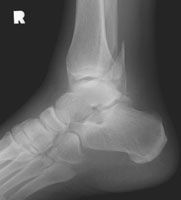

The Weber classification is used to determine the severity of tibiofibular ligament injury by the level of fibular fracture. The Weber B fracture consists of a fracture of the fibula near the joint and a transverse fracture of the medial malleolus (or disruption of the deltoid ligament). This results in partial disruption of the tibiofibular ligament complex and is from supination-lateral rotation injury.

- Click on the image for a larger versionALateral radiograph of the ankle. There is a fibular fracture, near the level of the tibiotalar joint.